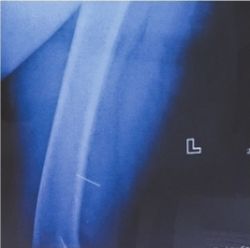

刺入刘阿婆腿里的绣花针。

冯世波供图

绣花针是什么时候“跑”进身体内的?刘阿婆告诉医生,自己平时爱做针线活,最近一次用针是在7月6日。那天坐在沙发上赶制空调被,完工后躺在沙发上小睡了一会。冯世波分析,很可能是刘阿婆小憩时,遗留在沙发上的针不经意间戳入体内。由于绣花针比较细,老人感觉又比较迟钝,当时她并没有察觉。“难怪后来我到处找针,都没有找到。”听了医生的话,刘阿婆这才想起当时确实忘记收拾针线了。冯世波给刘阿婆打了破伤风抗毒素后,在C臂X光机的引导下,顺利地将长约3厘米的绣花针取出。